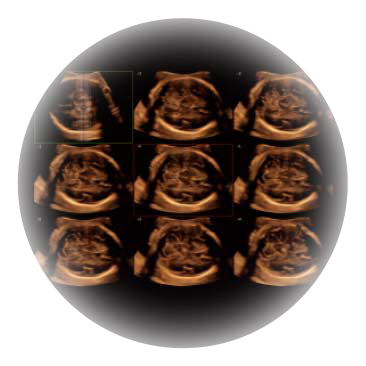

可同时显示组织结构表面和内部的轮廓信息,达到透视效果,为临床提供更丰富的诊断信息。

自动获取标准切面,自动完成测量,帮助医生快速完成检查,同时提升测量准确性。